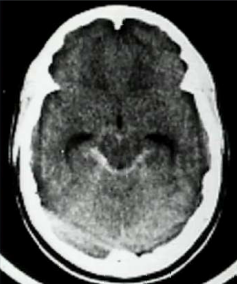

A 47 year old woman comes to the ED at 2am with a thunderclap headache and GCS of 13. Her CT scan is shown below. What are the primary causes of this patient’s headache?

Rupture of berry aneurism at arterial junctions and head injury can cause sub-arachnoid hemorrhage.